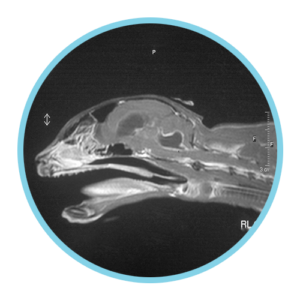

Neurological FIP